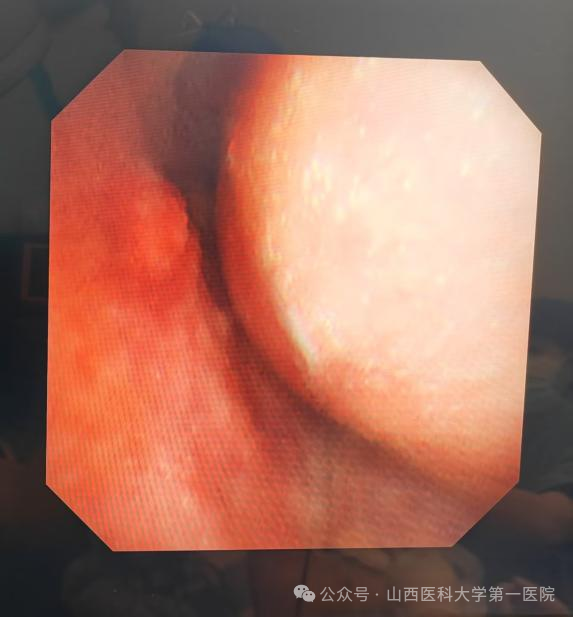

支气管镜下可见气管上端重度狭窄

当日晚上9点,呼吸介入团队成员任寿安、郭志宏、尹建升、李艳青、王琛在手术室为患者在局部麻醉下行支气管镜检查,发现气管上段呈新月形外压性狭窄,管腔狭窄约95%,任寿安、郭志宏主任医师迅速置入气道支架,完全覆盖狭窄部位,麻醉科郭志佳副教授全程保驾护航。整个过程有惊无险,患者呼吸困难得到明显改善,平卧返回重症医学科密切观察。

呼吸介入治疗后管腔通畅